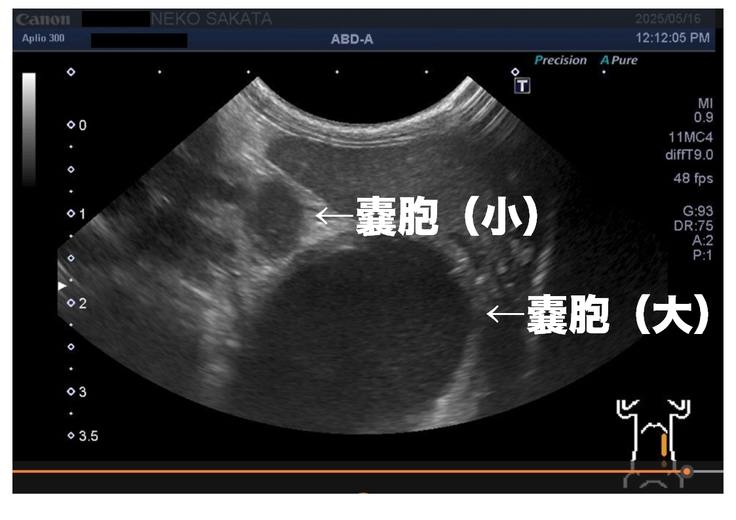

原因追及のためにエコー検査をしてもらった所、

お腹に大きな嚢胞が一つ、その横に小さな嚢胞が一つ見つかった。

エコーでは正体が分からない為、CTの設備がある病院で検査をすることを勧められる。